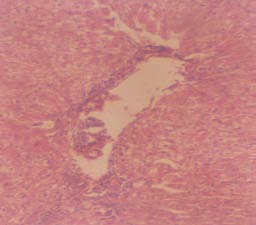

Experimental rabbits were dissected on the 9th day after administration of saponin. The method describe by Patel et al. (2010) was employed for the dissecting. They were killed by chloroform anesthesia and dissected. The small and large intestine, liver and kidneys were removed separately and cut into sections, The sections were fixed directly on a slide, stained with haematoxylin and eosin, examined and photographed.

The effect of saponin on the activity of serum, liver and kidney enzymes in controlled and experimental groups of rabbits is shown in Table 4 indicating the activity of marker enzymes (AST and ALT). Slight differences were observed in the activity of enzymes in all the groups of rabbits tested. The result of the histopathological studies of the liver, kidney and small intestine of treated and untreated rabbits is shown in figs 1, 2 and 3 respectively. The liver, small intestine and kidney of the untreated rabbits showed no visible lesion, but there were sectioning artifacts (figs 1(a), 2(a) and 3 (a)). In the treated liver, there was a mild periportal lymphocytic and histiocytic cellular infiltration (Fig 1b). In the kidney, there are multiple foci of haemorrhages into the intertitium. There were few loci of tubular necrosis and presence of hyaline casts with interstitial cellular infiltration by macrophages (fig 2b), and small intestine of the treated rabbits there were marked hyperplasias of the mucosal layer (Fig 3b).

It has been reported that renal dysfunction may be the cause of raised plasma, urea, uric acid and creatinine level accompanied by lowered urine urea, uric acid and creatinine level in high dose of drug treated rabbits (Adesokan and Akanji, 2004). Raised urea and non-protein nitrogen level in blood have been observed with impaired renal function or in acute renal failure (Adebayo et al., 2003). In the present study, the observed differences in the urinary contents are not significant. This difference may be due to the concentration of saponin used in the treatment. Zhongguo et al. (2005) found that concentrationdependent response was noticed when Quallaja saponin was used to treat E. coli K-12-infected wistar rats and that saponin from various sources differ in their biological activity. The initial increase observed in the blood glucose level was suspected to be due to the high percentage of sugar moiety that makes the chemical structure of saponins (Francis et al., 2002).

The presence of hyaline cast in the kidney is normal and has been ascribed to the use of medicines (Medline Plus Medical Encyclopaedia). The appearance of a few loci tubular necrosis in the kidney has been observed to be a reflection of the initial pathogenesis of the infection; indicating damage to the renal tubular epithelial cells. This condition is normal and not caused by the saponin therapy but a clinical manifestation of the disease. The description of renal tubular necrosis as one of the pathogenesis of clinical manifestation of typhoid fever has been made (Nishiura et al., 2005) and this substantiates the observations made in this study. The binding of saponins to bile acids in the intestine could reduce the availability of bile acids to the microbial population, thus reducing the formation of carcinogenic substances in the colon (Nishiura et al., 2005) that may lead to necrosis.